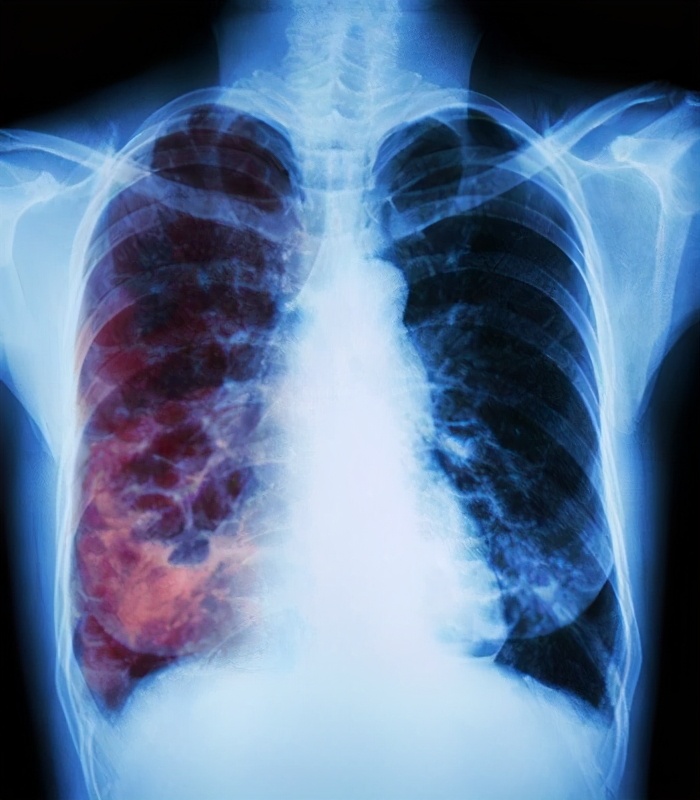

再次来到医院检查核酸和抗体还是阴性的,细心的医生询问了病史,做了胸部放射线检查,最后建议患者去传染病医院看一下。

在我国县级以上的地区都会设有结核病防治中心,在这里,只要是可疑肺结核的患者,都会免费做胸片和痰涂片等检查。